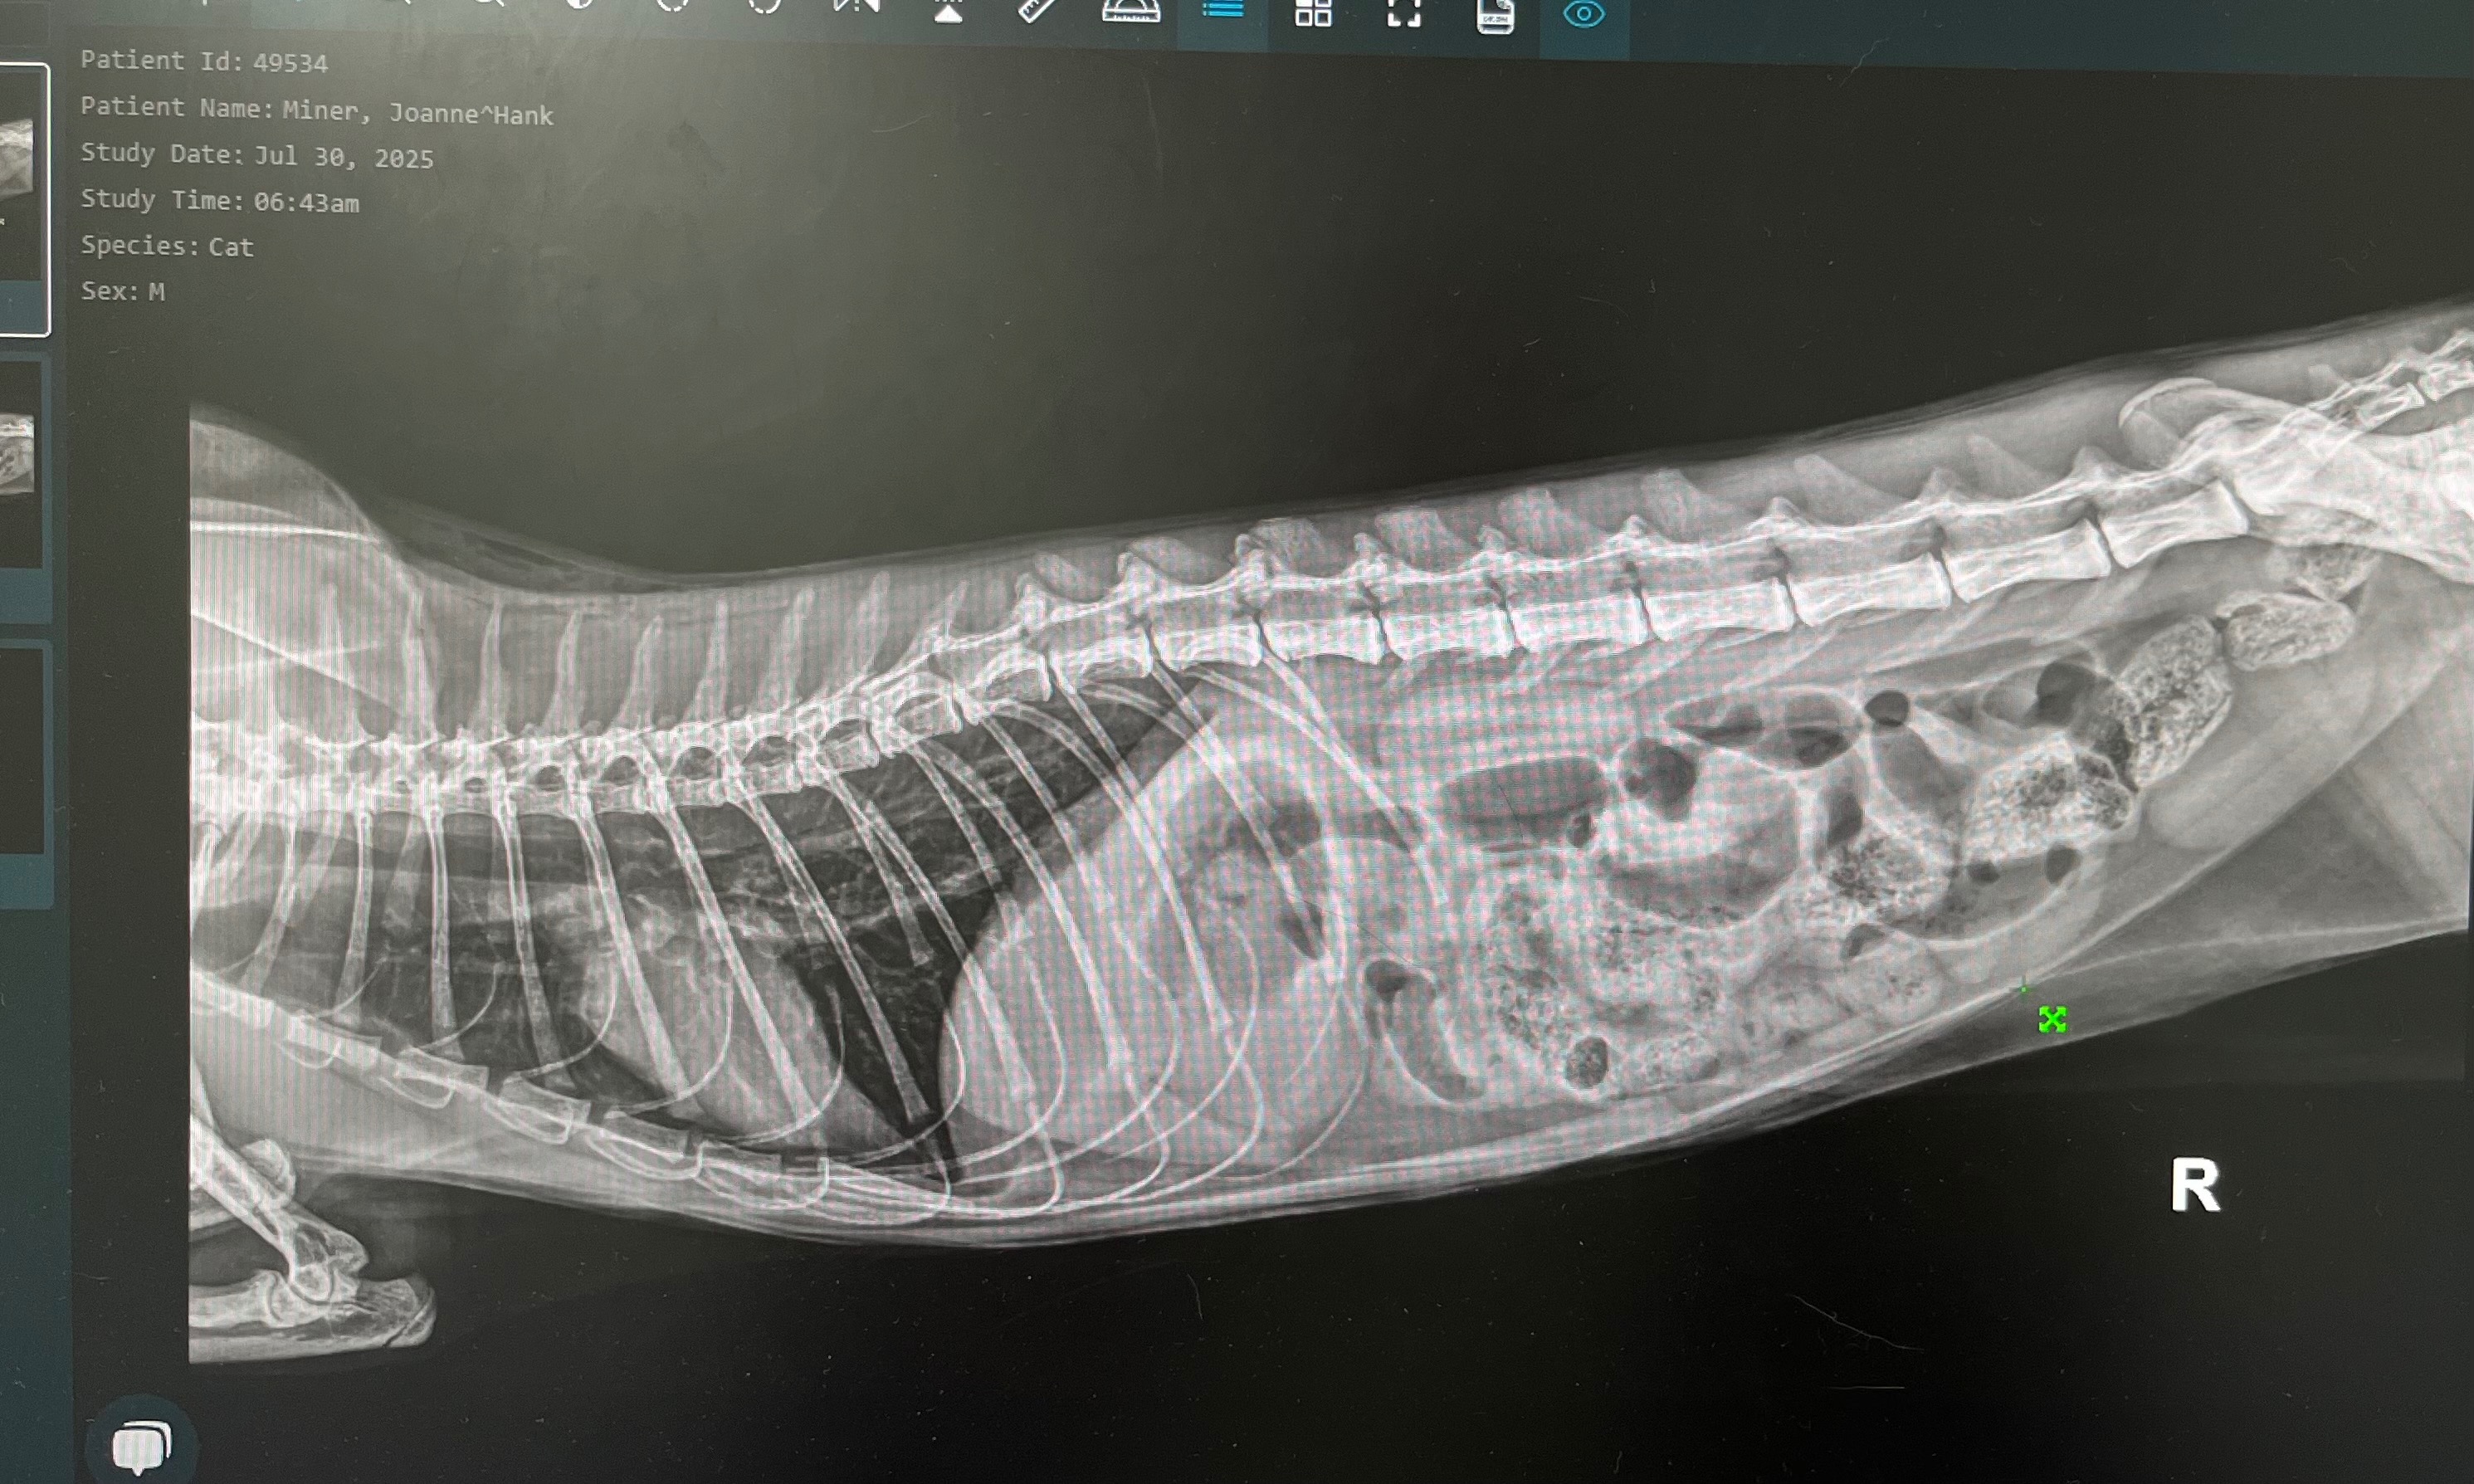

This is Hank, our sweet, timid 11-month-old kitten who has brought nothing but love and comfort into our lives. Hank is facing a life-threatening medical emergency: he has a bowel blockage that has torn part of his intestine. He needs urgent surgery to remove the damaged section of his bowel and repair it in order to survive.